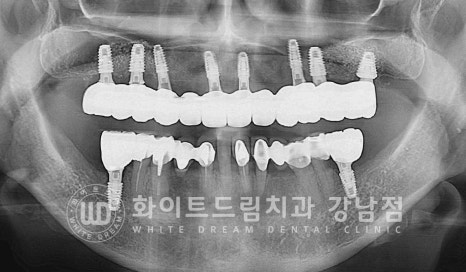

▲ 상악 풀케이스임플란트 수술 후 촬영한 x-ray

수술일자 : 24.02.06

우리는 한 악당 14개의 치아를 가지고 있습니다. (사랑니 제외)

이 중 식립되는 임플란트의 개수는 치아 개수의 60%를 식립한다고

생각하시면 되는데요.

보통 한 악당 8-9개 정도의 임플란트를 식립한답니다.

환자분도 총 8개의 임플란트를 식립했고, 상악동 거상술도 잘 진행되어

안정적이게 치유 상태를 보이는 상태입니다.

많은 양의 뼈이식이 들어갔고 초기 골소실이 심했던 부위이기에

1차 수술과 2차 수술을 나누어 진행했고

잇몸뼈의 골폭이 좁은 전치부는 직경 3.5mm의 미니 임플란트를 식립하고

어금니 부위는 직경 6mm의 와이드형 임플란트를 이용하여

고정력과 안정성을 높였습니다.

환자분처럼 6mm의 두꺼운 임플란트는 잘 사용하지는 않으나

초기 골 소실이 심해 고정력이 약한 경우는 직경이 넓은 임플란트를 선택하여

잇몸뼈와 접촉면적을 넓혀 고정력과 안정성을 높여주는 것도 하나의 좋은 선택이 될 수 있답니다.